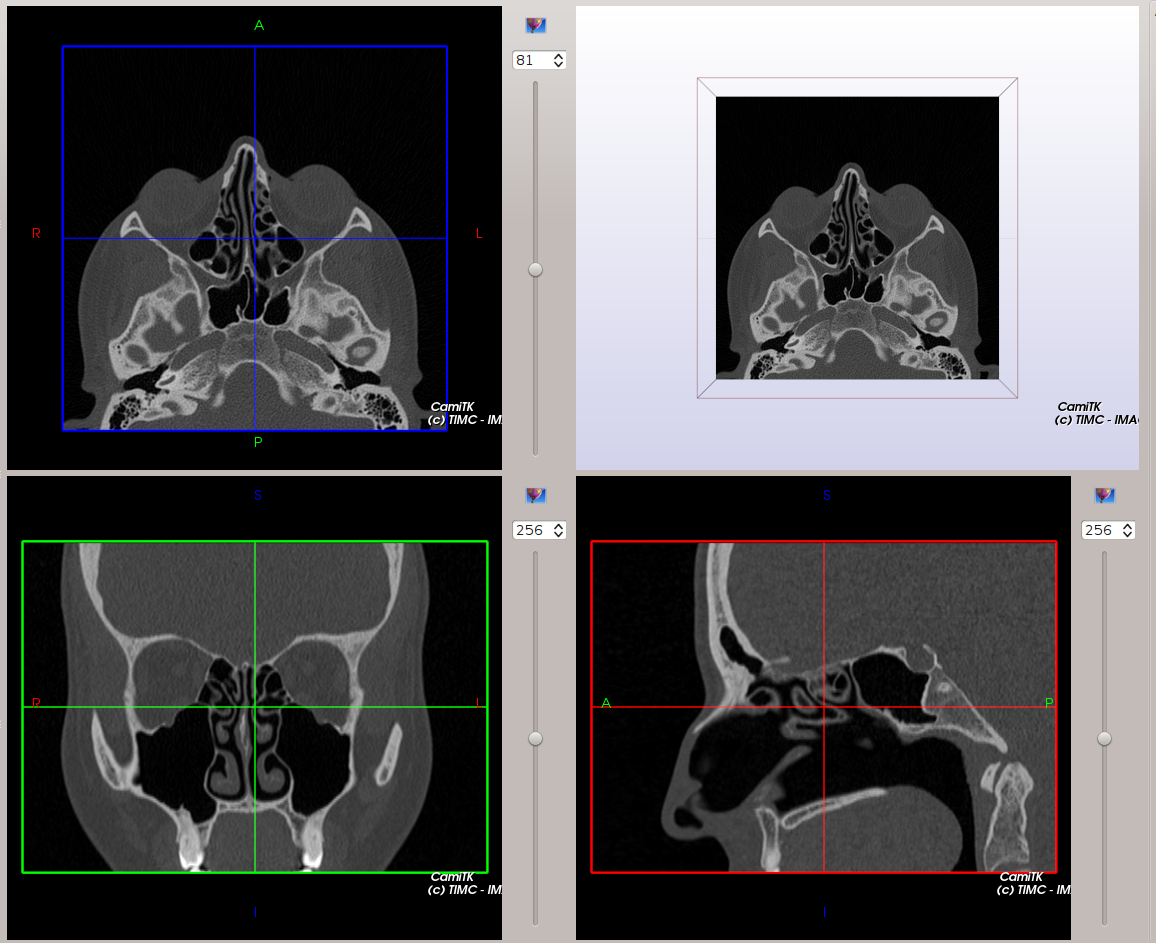

CamiTK slices visualization

The Axial, Coronal and Sagittal viewers are tagged with patient position (Anterior / Posterior, Superior / Inferior, Right / Left) in order to locate more easily each slice of the image.